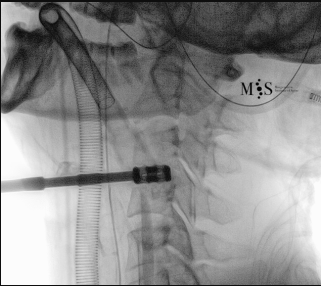

Imágenes de una cirugía de fusión cervical endoscópica

Animación de la inserción de una caja intersomática por vía endoscópica percutánea.

Nótese la apertura (expansión) de la pared posterior del disco al insertar la caja.